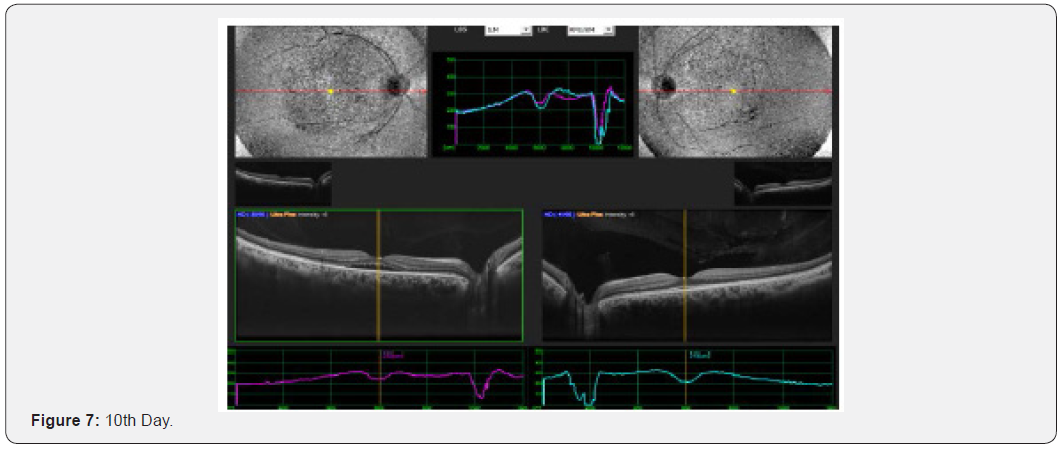

Results: This interventional study includes 21 patients who were diagnosed as acute CSC and followed from the day of presentation to 30th day. All 21 patients were undergoing intervention by using topical bromfenac eye drop, one drop twice daily for 30 days. Macular thickness and visual acuity recorded from the day of presentation up to 30th day. (Table 6) shows all changes before and after treatment and (Figure 1-4) shows early resolution of sub-macular fluid in one of these patients treated with topical bromfenac eye drops (one drop twice daily). In group 1 the macular thickness (CFT) improve from 422-485 microns at onset to 317-382 microns on 5th day becomes 246-295 on 10th day while 210-226 on 30th day. Vision improved from 0.4 to 0.7 at 5th day, improved to 0.8 on 10th day and remained same on 30th day. In group 2 the CFT reduced from 535-565 microns to 401-440 microns on 5th day becomes 318310 on 10th day and on 30th day it was 221-232 microns with improvement in visual acuity which was 0.2 at onset to 0.6 at 5th day, 0.7 at 10th day and improved to 0.8 on 30th day. In group 3 the CFT reduced from 657-722 microns to 456-469 microns on 5th day, 259-366 microns on 10th day while 206-227 microns on 30th day. Visual acuity improved from CF at onset to 0.4 on 5th day, 0.6 on 10th day and improved to 0.7 on 30th day. Conclusion: This, simple, safe, affordable and easily available treatment modality in all parts of the world with early rehabilitation of acute CSC patients.

This interventional retrospective as well as prospective study includes 21 patients who were diagnosed as acute CSC and followed from the day of presentation to 30th day. All 21 patients were undergoing intervention by using topical bromfenac eye drop, one drop twice daily for 30 days. Macular thickness and visual acuity recorded from the day of presentation up to 30th day. (Table 6) shows all changes before and after treatment and (Figure 1-8) shows early resolution of sub-macular fluid in one of these patients treated with topical bromfenac eye drops (one drop twice daily). In group 1 the macular thickness (CFT) improve from 422-485 microns at onset to 317-382 microns on 5th day becomes 246-295 on 10th day while 210-226 on 30th day. Vision improved from 0.4 to 0.7 at 5th day, improved to 0.8 on 10th day and remained same on 30th day. In group 2 the CFT reduced from 535-565 microns to 401-440 microns on 5th day becomes 318-310 on 10th day and on 30th day it was 221-232 microns with improvement in visual acuity which was 0.2 at onset to 0.6 at 5th day, 0.7 at 10th day and improved to 0.8 on 30th day. In group 3 the CFT reduced from 657-722 microns to 456-469 microns on 5th day, 259-366 microns on 10th day while 206-227 microns on 30th day. Visual acuity improved from CF at onset to 0.4 on 5th day, 0.6 on 10th day and improved to 0.7 on 30th day.